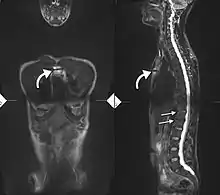

Lateral X-ray of the mid back in ankylosing spondylitis

Lateral X-ray of the neck in ankylosing spondylitisImaging

X-ray showing bamboo spine in a person with ankylosing spondylitis

CT scan showing bamboo spine in ankylosing spondylitis

T1-weighted MRI with fat suppression after administration of gadolinium contrast showing sacroiliitis in a person with ankylosing spondylitis